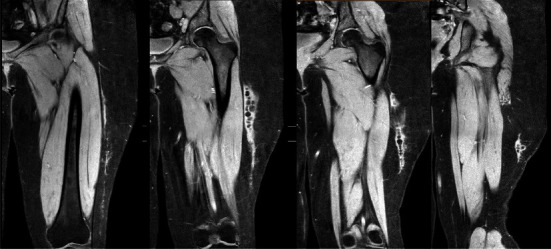

Morel-Lavallée lesions are serious internal degloving injuries associated with trauma. Its diagnosis and treatment can be challenging. We describe the surgical treatment of a case of a chronic Morel-Lavallée lesion in a pediatric patient who sustained an injury to her left thigh during an all-terrain vehicle accident more than a year ago.